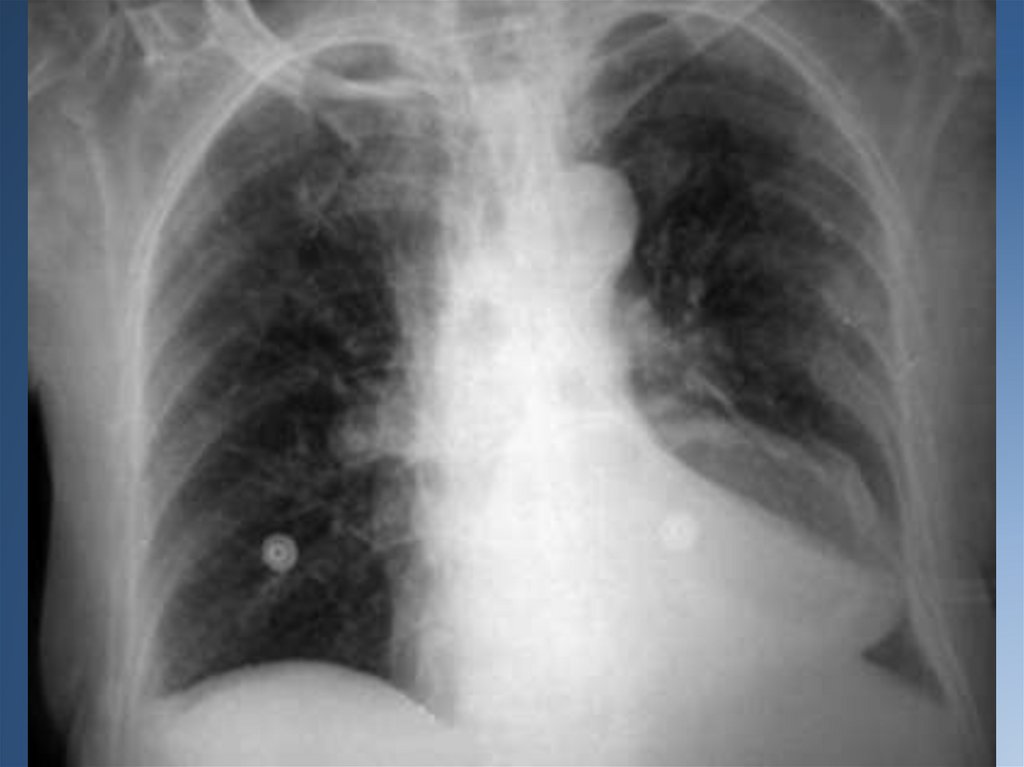

АБСЦЕСС ЛЕГКОГО

Абсцесс легкого – это гнойное расплавление легочной ткани с

образованием одной или нескольких отграниченных полостей,

заполненных гноем и окруженных воспалительным валиком

(перифокальное воспаление – инфильтрат).